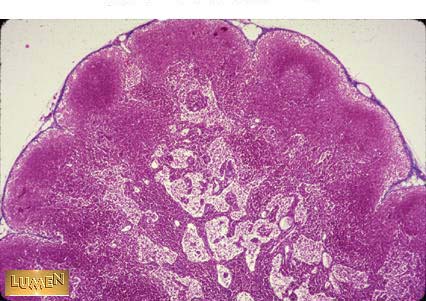

What organ is this?

Lymph Node